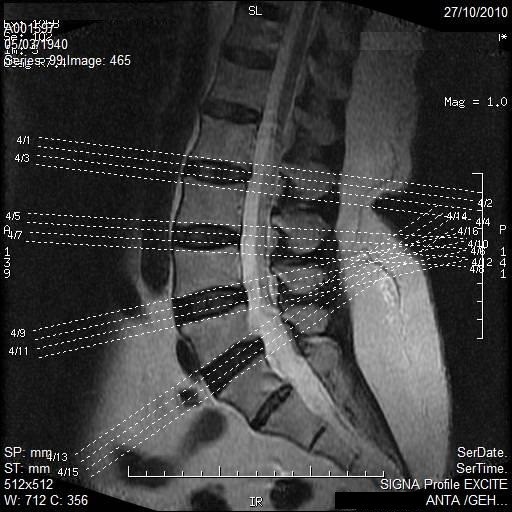

Una resonancia magnética puede ser un paso importante para el diagnóstico de la patología de su columna vertebral. Nuestros técnicos están capacitados y se preocupan por las personas, con el deseo de hacer que su prueba sea tan exitosa y cómoda como sea posible. Nuestro personal médico responderá con gusto cualquier pregunta que usted tenga antes de su resonancia magnética.